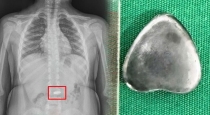

காலையில் கண் விழித்ததும் பயங்கர தொண்டை வலி! தூக்கத்தில் இப்படியா செய்வது.... மருத்துவர்களையே அதிர்ச்சியாக்கிய எக்ஸ்ரே ரிப்போர்ட்! நிமிடத்தில் மாறிய வாழ்க்கை... மிரண்டு போன குடும்பம்!!!